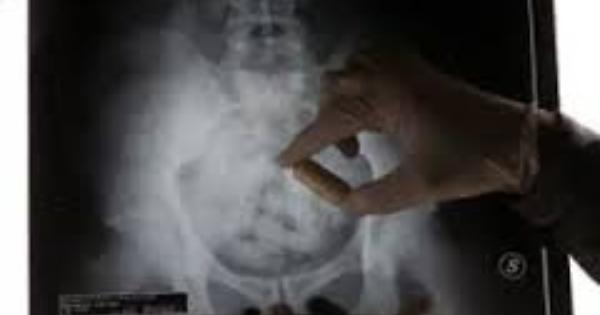

Appena tornato da Santo Domingo, Matteo Lombardi aveva ingerito tre ovuli di polvere bianca dal peso complessivo 30 grammi

radiografia ovuli nell'addome

Matteo Lombardi aveva ingerito tre ovuli, verosimilmente contenenti droga, per un peso di 30 grammi. E' stato ricoverato e piantonato e con il passare delle ore ha espulso altri due ovuli, che effettivamente contenevano cocaina. Per lui, oltre all'accusa di detenzione a fini di spaccio di stupefacenti che ha portato all'emissione dell'ordinanza, si annuncia quindi quella traffico internazionale.